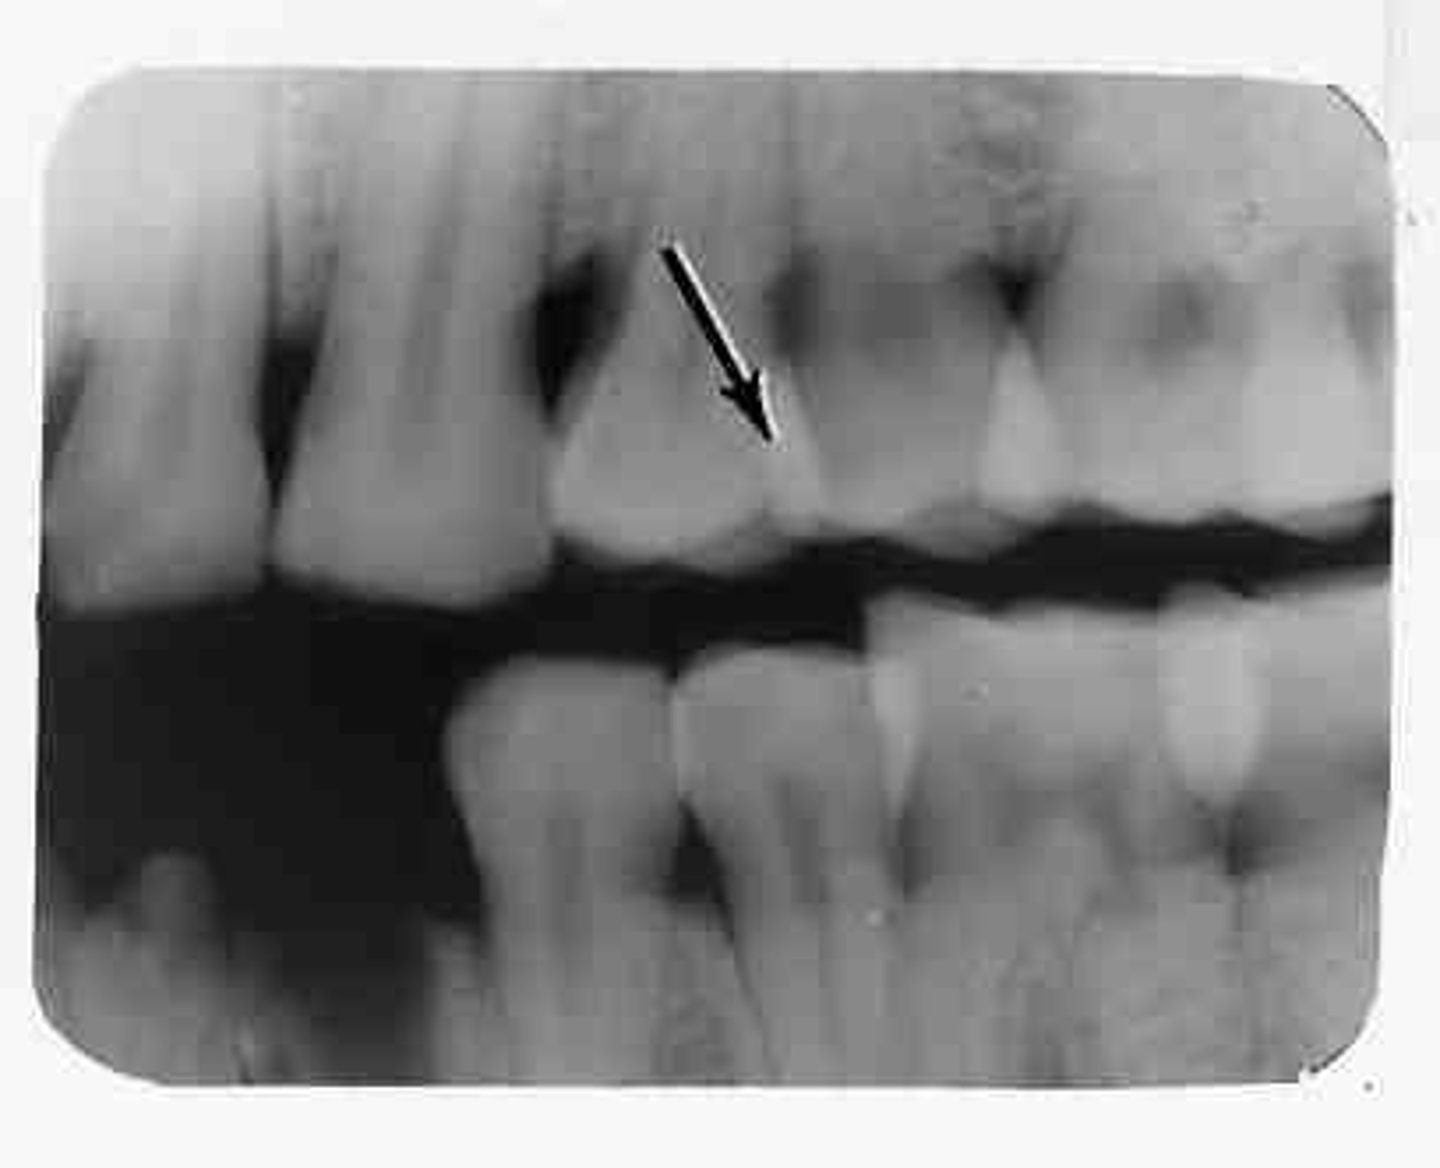

Overlapped interproximal contacts

Result from incorrect horizontal angulation; be sure to direct the x-ray beam through the interproximal regions.

<p>Result from incorrect horizontal angulation; be sure to direct the x-ray beam through the interproximal regions.</p>